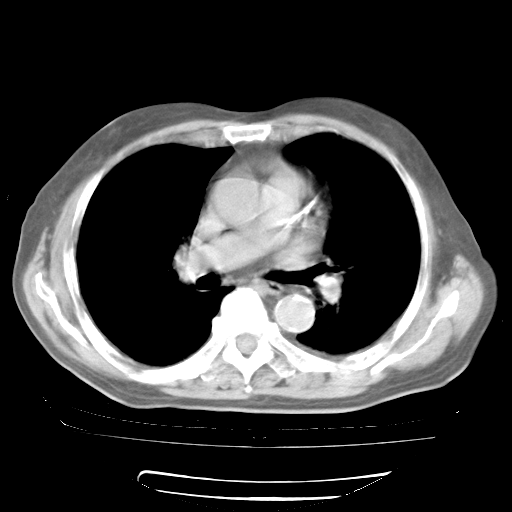

4月28日肺部CT——再次出现类似去年5月9日——磨玻璃样、间有“粟粒样”改变。

4月28日肺部CT